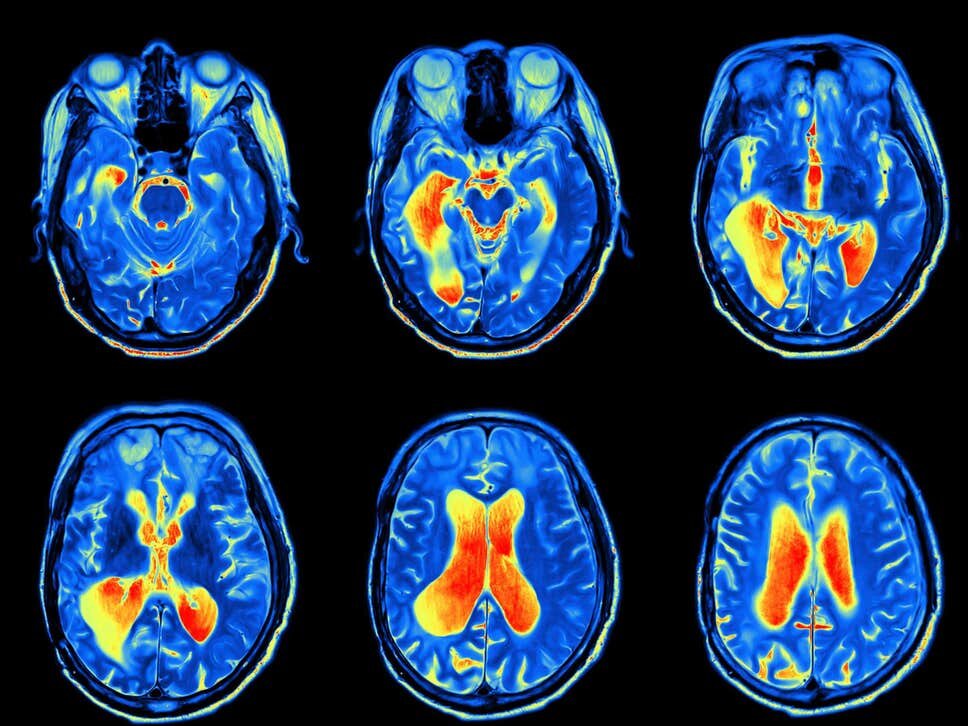

Researchers from the German Centre for Neurodegenerative Diseases followed 2,013 adults from 1997 through to 2012. Their cardiorespiratory fitness was measured using peak oxygen uptake while participants used an exercise bike. MRI scans of their brain were then analysed.